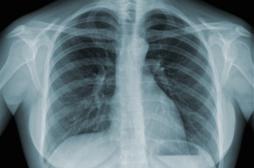

LES MALADIES

SYMPTÔMES